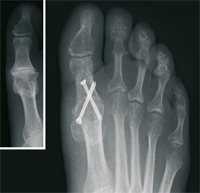

Claw Toe

The claw toe or hammer toe describes a deformity or curvature of the small toe. By increasing the shortening first digital flexor tendon in the middle joint, then the extensor tendon in the base joint, there is a curvature of the toe. In this way, pain and cornifications occur under the ball of the foot, and painful pressure points on the interphalangeal joints (corns). This deformity can usually only be corrected surgically. By an extension of the extensor tendon and solution of the joint capsule, together with a stiffening means in the toe joint, the toe is straightened permanently. The pressure points and relieves pain.